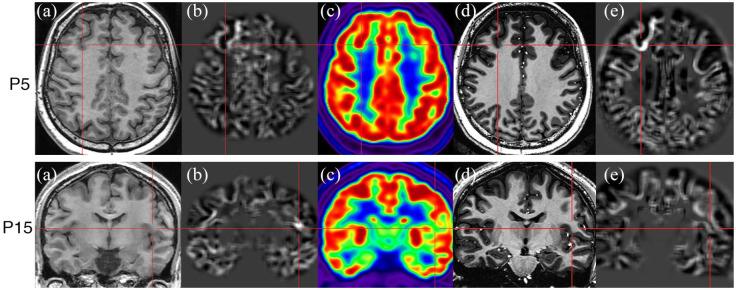

7T MRI evaluation confirmed the lesion in nine of the 11 (81.8%) patients with suspicious lesions on 3T MRI. It also revealed new lesions in four of the 24 (16.7%) strictly MRI-negative patients. Histopathology showed FCD type II in 11 of the 13 (84.6%) 7T MRI-positive cases. Unexpectedly, three of the four newly identified FCD lesions were located in the posterior quadrant. Blurred gray-white boundary was the most frequently observed sign of FCD, appearing on 7T T1W image in all cases and on T2W and FLAIR images in only about half cases. The 7T junction map successfully detected FCD (10/11) in more cases than the extension (1/11) and thickness (0/11) maps. The 3D T1W images at 7T exhibited superior cerebral gray-white matter contrast, more obviously blurred gray-white boundary of FCD, and larger and brighter positive zones in post-processing than 3T T1W images.